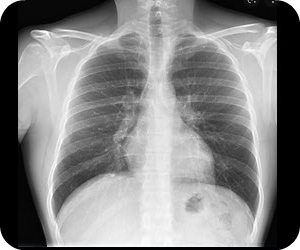

Estudio sobre las formas y el funcionamiento de las diferentes estructuras del cuerpo humano, estudios por imágenes para obtener imágenes del interior de su cuerpo, se pueden usar para diagnosticar y tratar enfermedades y lesiones. Los tejidos de su cuerpo cambian los patrones de energía para producir una imagen o fotografía.